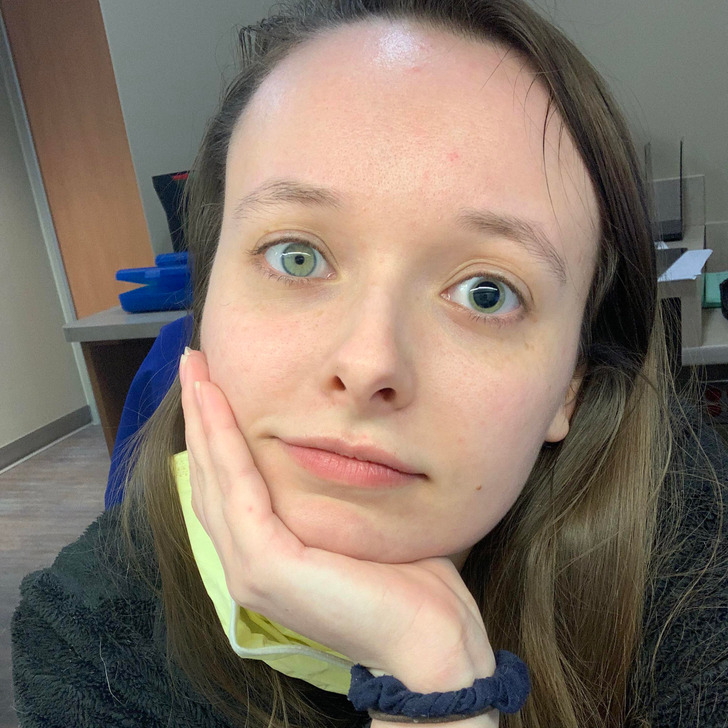

#7 Trpím anazokóriou – ak sa vyvinie, môže to znamenať tlak v mozgu, mŕtvicu alebo iný vážny stav